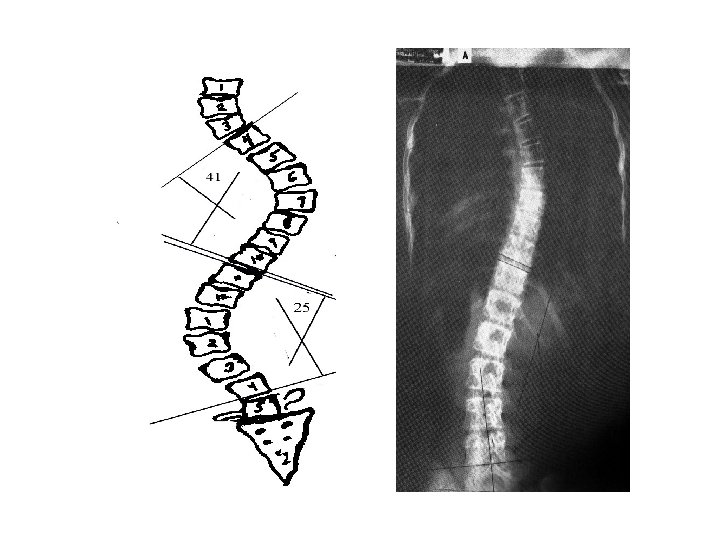

Cobb’s Angle –Locate the maximally tilted vertebral bodies in the curvature in the AP-PA projection –Draw a line through the top end plate of the most superior and bottom end plate of most inferior vertebrae involved towards the concavity. –Construct perpendicular lines through these and measure the acute angle

§ Draw a line through the top end plate of the most superior vertebrae, and through the bottom end plate of most inferior vertebrae. . . toward the concavity.

A: Thoracic - 41° Lumbar - 25° X-ray B Twelve minutes after X-ray A B: Thoracic - 13° Lumbar - 9°